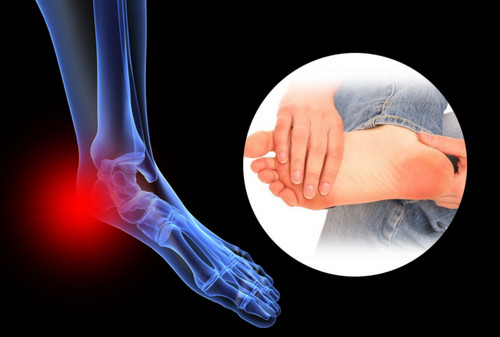

족저 근막염이란?

족저근막염은 발바닥 뒤꿈치에 염증이 생기면서 나타나는 통증을 말합니다. 남성보다 여성에게 약 2배 정도 더 많이 발생한다고 하며, 과도한 발의 스트레스나 무리한 운동이 주요 원인으로 알려져 있습니다. 이 밖에도 급격한 체중 증가나 평발 역시 발병 위험을 높이는 요인이 됩니다.

족저 근막염의 가장 흔한 증상은 아침에 통증이 특히 심하다는 점입니다. 밤사이 수축된 족저근막이 아침에 첫 발을 디디며 갑자기 늘어나 통증이 생기기 때문입니다. 대개 종아리 근육이 짧아지면서 발바닥 근막이 당겨져 발생하는 경우가 많습니다. 따라서 예방을 위해서는 평소 종아리와 발바닥을 함께 관리하는 것이 중요합니다. 이미 증상이 있다면 생활습관 개선과 더불어 필요에 따라 약물이나 의료적 치료를 병행해야 합니다.